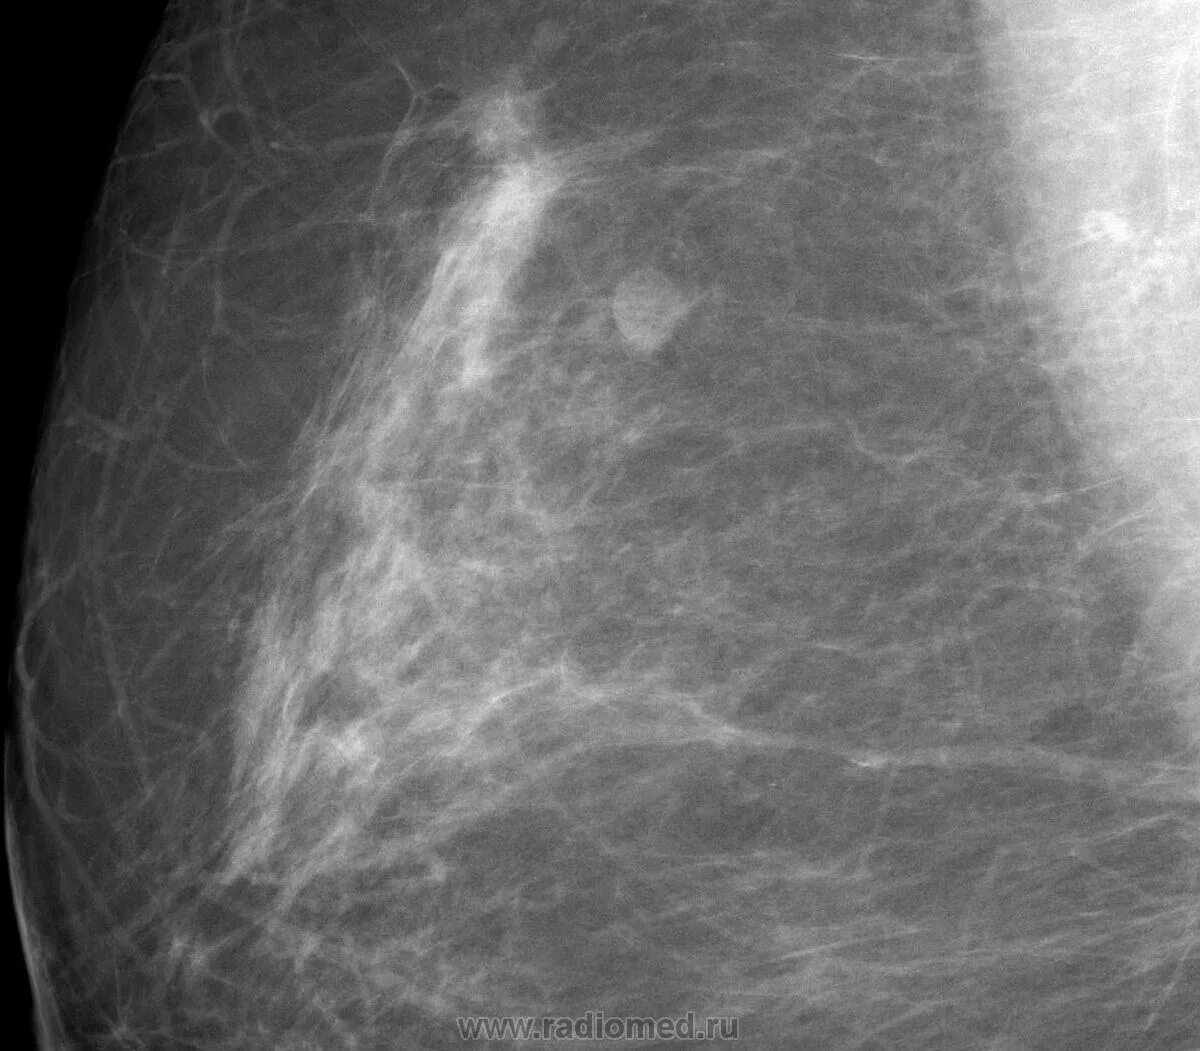

Маммография молочных желез объемное образование. опухоль молочной железы. онкология молочной железы. опухольмолочныйжелезы.

Карцинома молочной железы маммография. опухольмолочныйжелезы. опухоль молочного железа.

Раковая опухоль маммография. маммография опухоль молочной железы.